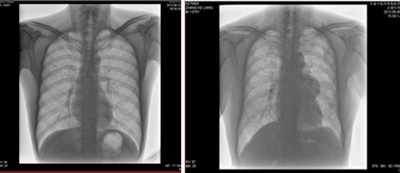

★適用于全身各部位攝影,包括常規攝影(立位攝影、臥位攝影等,如胸片、頸椎、腰椎、腹部、頭顱、四肢等)和特殊攝影(傾斜攝影、角度攝影等,如瓦氏位、骶髂關節、髕骨軸位、跟骨軸位等)。

★全身各部位透視(如胸透、腹透等)、透視下定位、透視下穿刺及透視下數字點片攝影。